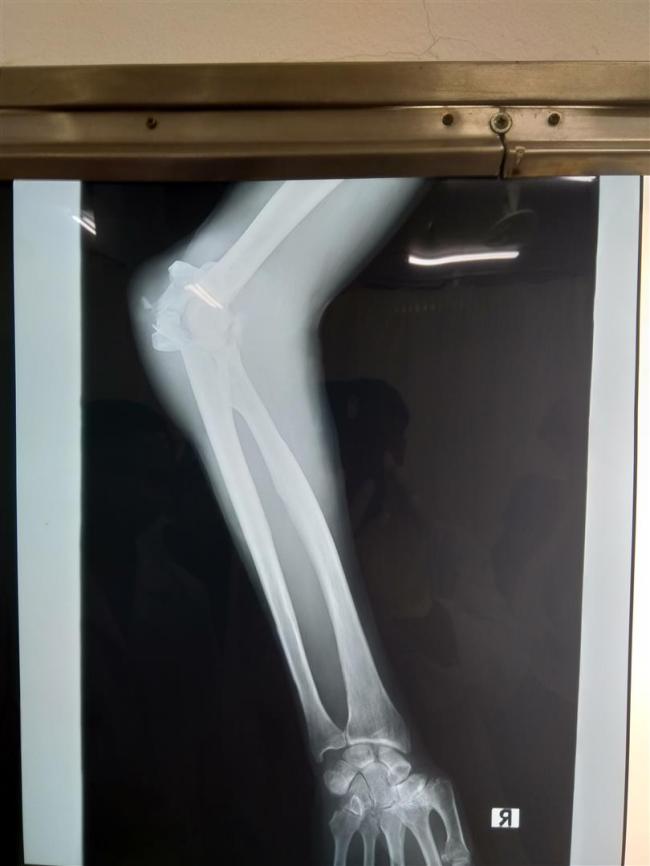

X-Ray taken in Luang Prabang. It doesn’t look too bad.

The x-ray taken at Bangkok Hospital showed just how bad things were.

Next day was to be a very busy one. Because I’d had a motorcycle accident they decided to check all areas that might have been affected – head, neck, pelvis and abdomen. X-rays and CT scans on the bony areas, ultra sound on the soft parts. I was taken down for a full cardiogram and then an extremely comprehensive lung capacity test. There was nothing to worry about in any of those and I was pleased to have confirmed that my lungs work to full capacity given that I have mild asthma. The orthopaedic surgeon came to see me and explained how badly damaged my elbow was. The top of the ulna and the radius were both smashed up and the cup at the top of each bone, where they sit against the humerus, were partially broken off. He was confident he could effect repairs but didn’t know how things would be in the future. “Will I be able to ride my bike?”, was my immediate question. “Yes, but it’s likely to be painful. That’s because the cartilage in the joints has been damaged and some will be missing”, he explained. “But only time will tell.” He said they needed to operate straight away, otherwise inflammation quickly sets in and that makes operating more difficult. So at 2pm I was taken down for surgery. The anaesthetist explained what she was going to do, in went the needle and out went the lights.

I came round at about 21.15, after six and a half hours in surgery. I was in lots of pain and discomfort and spent the night drifting in and out of sleep, constantly asking for pain relief. By the morning the pain was worse! A doctor came round and adjusted the plaster splint, bringing immediate relief to my swollen arm and hand. They also set up a self managed morphine supply. That was nice! The surgeon came to talk me through what he’d done and he showed me the x-ray so I could see all the metalwork inside. He checked that I could move my hand and fingers satisfactorily, meaning that there was no nerve damage. I’d be stuck with the plaster splint for four weeks, then I’d get a light weight plastic and metal splint, enabling me to start moving the elbow. It would be around four to five months before I’d be able to ride my bike. He explained how some of the cartilage had been carried away by the broken bone and that because it had no blood supply, would not be able to repair itself. The operation wounds had been stapled together and he cleaned them up then put the splint back on. The x-rays will give you an idea of how bad the damage to the bones is.